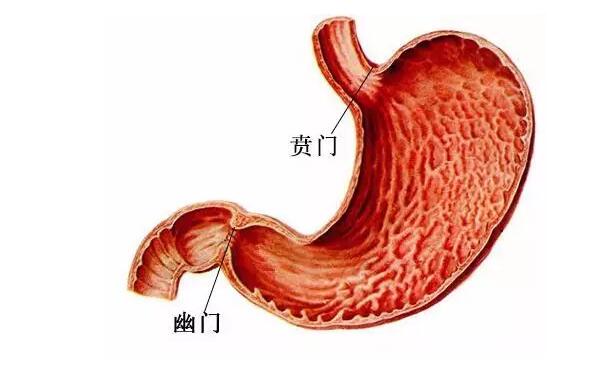

成人胃的入口(贲门)比较紧,而出口(幽门)松。吃完饭后,入口的肌肉会立刻收紧,不管怎么运动,胃里的食物都不会轻易吐出来。再加上出口的肌肉相对较松,食物很快就进入到肠子中了。

而新生儿和成人正相反,入口松、出口紧,吃的奶稍微一晃就返流出来了,所以特别容易溢奶、吐奶。不过这种生理现象会随着月龄的增长、贲门和幽门括约肌的发育而逐渐消失。